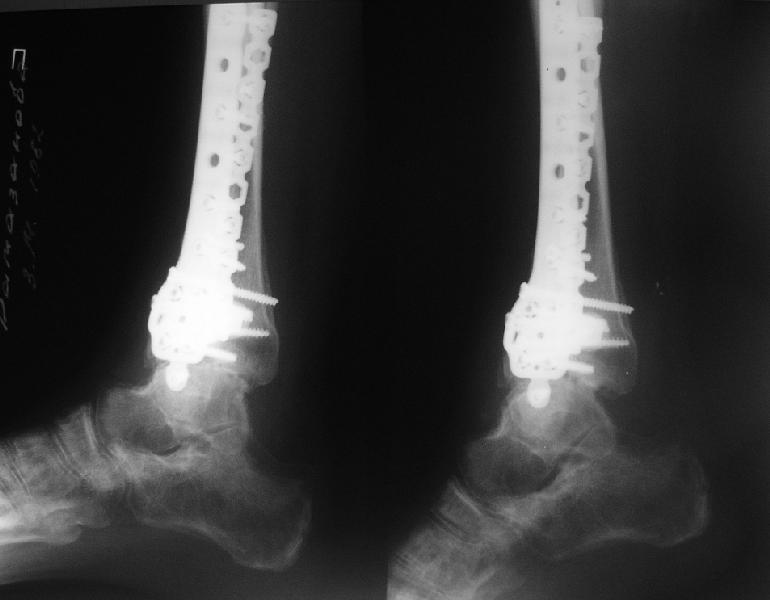

Обратилась женщина, 25 л. 8 мес. назад в одной из больниц сделан

остеосинтез пилона. На сегодня ходит без дополнительной опоры, хромая

на поврежденную ногу. Движения в голеностопном суставе еще есть.

Снимки в приложении.

Вопрос - что делать? Замыкать сустав пациентка пока не настроена

(наверно, получится настроить, если задаться такой целью). Нет ли

смысла попытаться сделать какую-то восстановительную операцию?

Допустим, получится устранить подвывих, восстановить межберцовые

соотношения - это что-то хорошее надолго даст? Или упросто убрать

"железо", и этим ограничиться, пока сама не придет за артродезом?

Есть ли здесь смысл пытаться организовать эндопротезирование? В

смысле, доступные сейчас протезы применимы в этой ситуации?